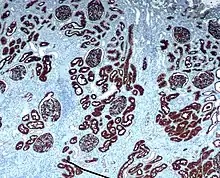

The most distinctive characteristic of the proximal tubule is its luminal brush border.

The luminal surface of the epithelial cells of this segment of the nephron is covered with densely packed microvilli forming a border readily visible under the light microscope giving the brush border cell its name. The microvilli greatly increase the luminal surface area of the cells, presumably facilitating their reabsorptive function as well as putative flow sensing within the lumen.[1] The microvilli are composed of actin filament bundles that have been visualized using confocal microscopy.[2]

Cuboidal epithelial cells lining the proximal tubule have extensive lateral interdigitations between neighboring cells, which lend an appearance of having no discrete cell margins when viewed with a light microscope.

This has led some observers to describe the lumen of proximal tubules as occluded or "dirty-looking", in contrast to the "clean" appearance of distal tubules, which have quite different properties.